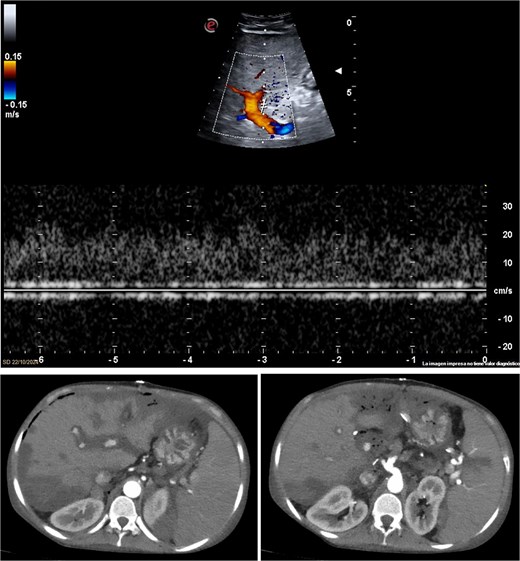

The patient received early antiplatelet therapy due to the high risk of thrombosis. Strict monitoring included lab tests and Doppler ultrasound every 12 h. On postoperative day 3, liver function tests showed no expected improvement, and Doppler failed to detect hepatic artery flow (Fig. 2a). An emergent CT angiography revealed proximal hepatic artery occlusion with multiple hypodense parenchymal areas, consistent with hypoperfusion and infarction (Fig. 2b). In the setting of acute graft failure, the patient was listed for emergency retransplantation. The retrieval process began within 12 h.

Imaging studies confirming hepatic artery thrombosis. (a) Doppler ultrasound showing absent hepatic artery flow. (b and c) CT angiography showing proximal hepatic artery occlusion with multiple hypodense areas in the liver parenchyma, consistent with ischemia and infarction.